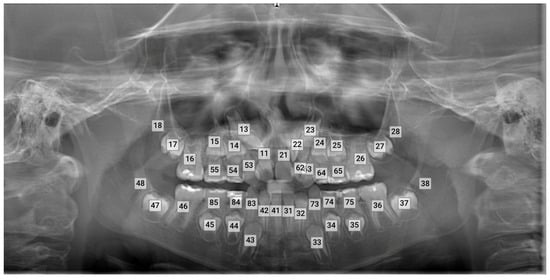

All panoramic radiographs were obtained using the Morita Veraviewepocs (Morita Corp., Kyoto, Japan) and subsequently uploaded to the Diagnocat software (DC, Diagnocat LLC, San Francisco, CA, USA, https://diagnocat.com/ accessed on 24 November 2024). A radiologic report for each radiograph was generated, which served as the basis for the automatic evaluation (Figure 1). Teeth detection and numbering were performed according to the FDI notation and analyzed by five different orthodontists. In this study, ground truth annotations, manual identification, and the labeling of the correct positions and numbering of teeth, were provided by one orthodontist with 20 years of experience, two with 10 years of experience, and two with 4 years of experience. These annotations served as the reference standard for evaluating the performance of the AI-based software.

Figure 1.

Teeth detection and numbering by the software.